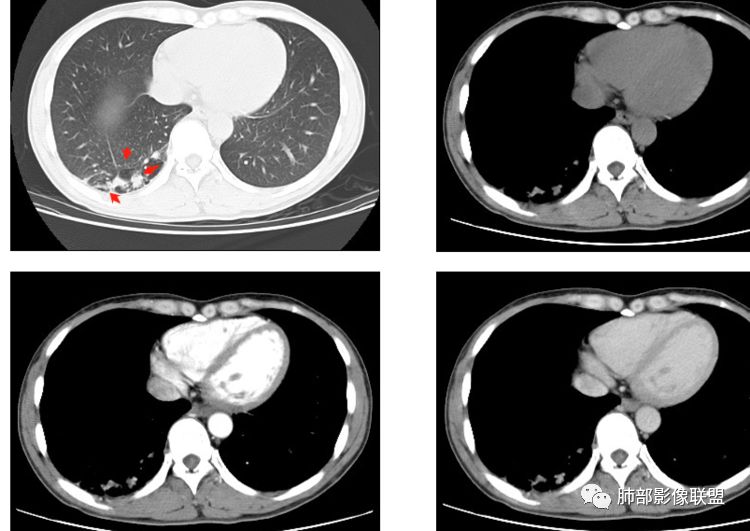

大雄:无强化,推移血管,排除结核与psp;平扫似有高密度

与支气管相通,则考虑曲霉粘液栓;不相通,可以考虑支气管闭锁或囊肿。

南边老师分析:

大家在讨论中提到以下疾病,归纳一下

1、恶性:鳞癌

2、先天发育异常:囊肿、支气管闭锁、隔离症

3、感染:结核、曲霉菌、炎性肉芽肿

4、良性肿瘤:PSP

我们一起捋一捋征象:

右肺下叶囊性病变,边缘光滑,薄环状强化,内壁较光滑

血管贴边

周围多发长索条

远端有斑片状条带状高密度影,周围肺气肿

附近胸膜增厚,内有血管影

南大病变影像分析:

这个病变和大家所想有些差异,这个图像还是不够薄,但是

第一,看支气管,有一条支气管从病变边缘走过,有一条支气管在病灶近端堵塞;说明病变和支气管有关系,一般情况下支气管堵塞应该考虑炎性病变或恶性肿瘤才可以符合,不符合良性肿瘤,当然肺囊肿也可以,因为它是先天发育变异的。

第二,看强化幅度,内无强化,但是我担心图像并不够薄,目测观察有所偏差,但是现可见薄壁样强化;从这个角度考虑,良性肿瘤就不符合了,如PSP就不太支持了,这个病变远端有分叶、有小尾巴,周围有索条状影,除非PSP合并感染,二元论,否则单纯PSP周围不会有这种表现。

第三,病变旁边胸膜区域有增厚,似乎有些血管增粗,虽然这不是隔离征好发区域;它应该偏内侧一点,但是我们应该最好有重建血管先排除隔离征;从所给图片看,病灶具体走形外面没有看见血管进入,因为是囊性病变嘛。